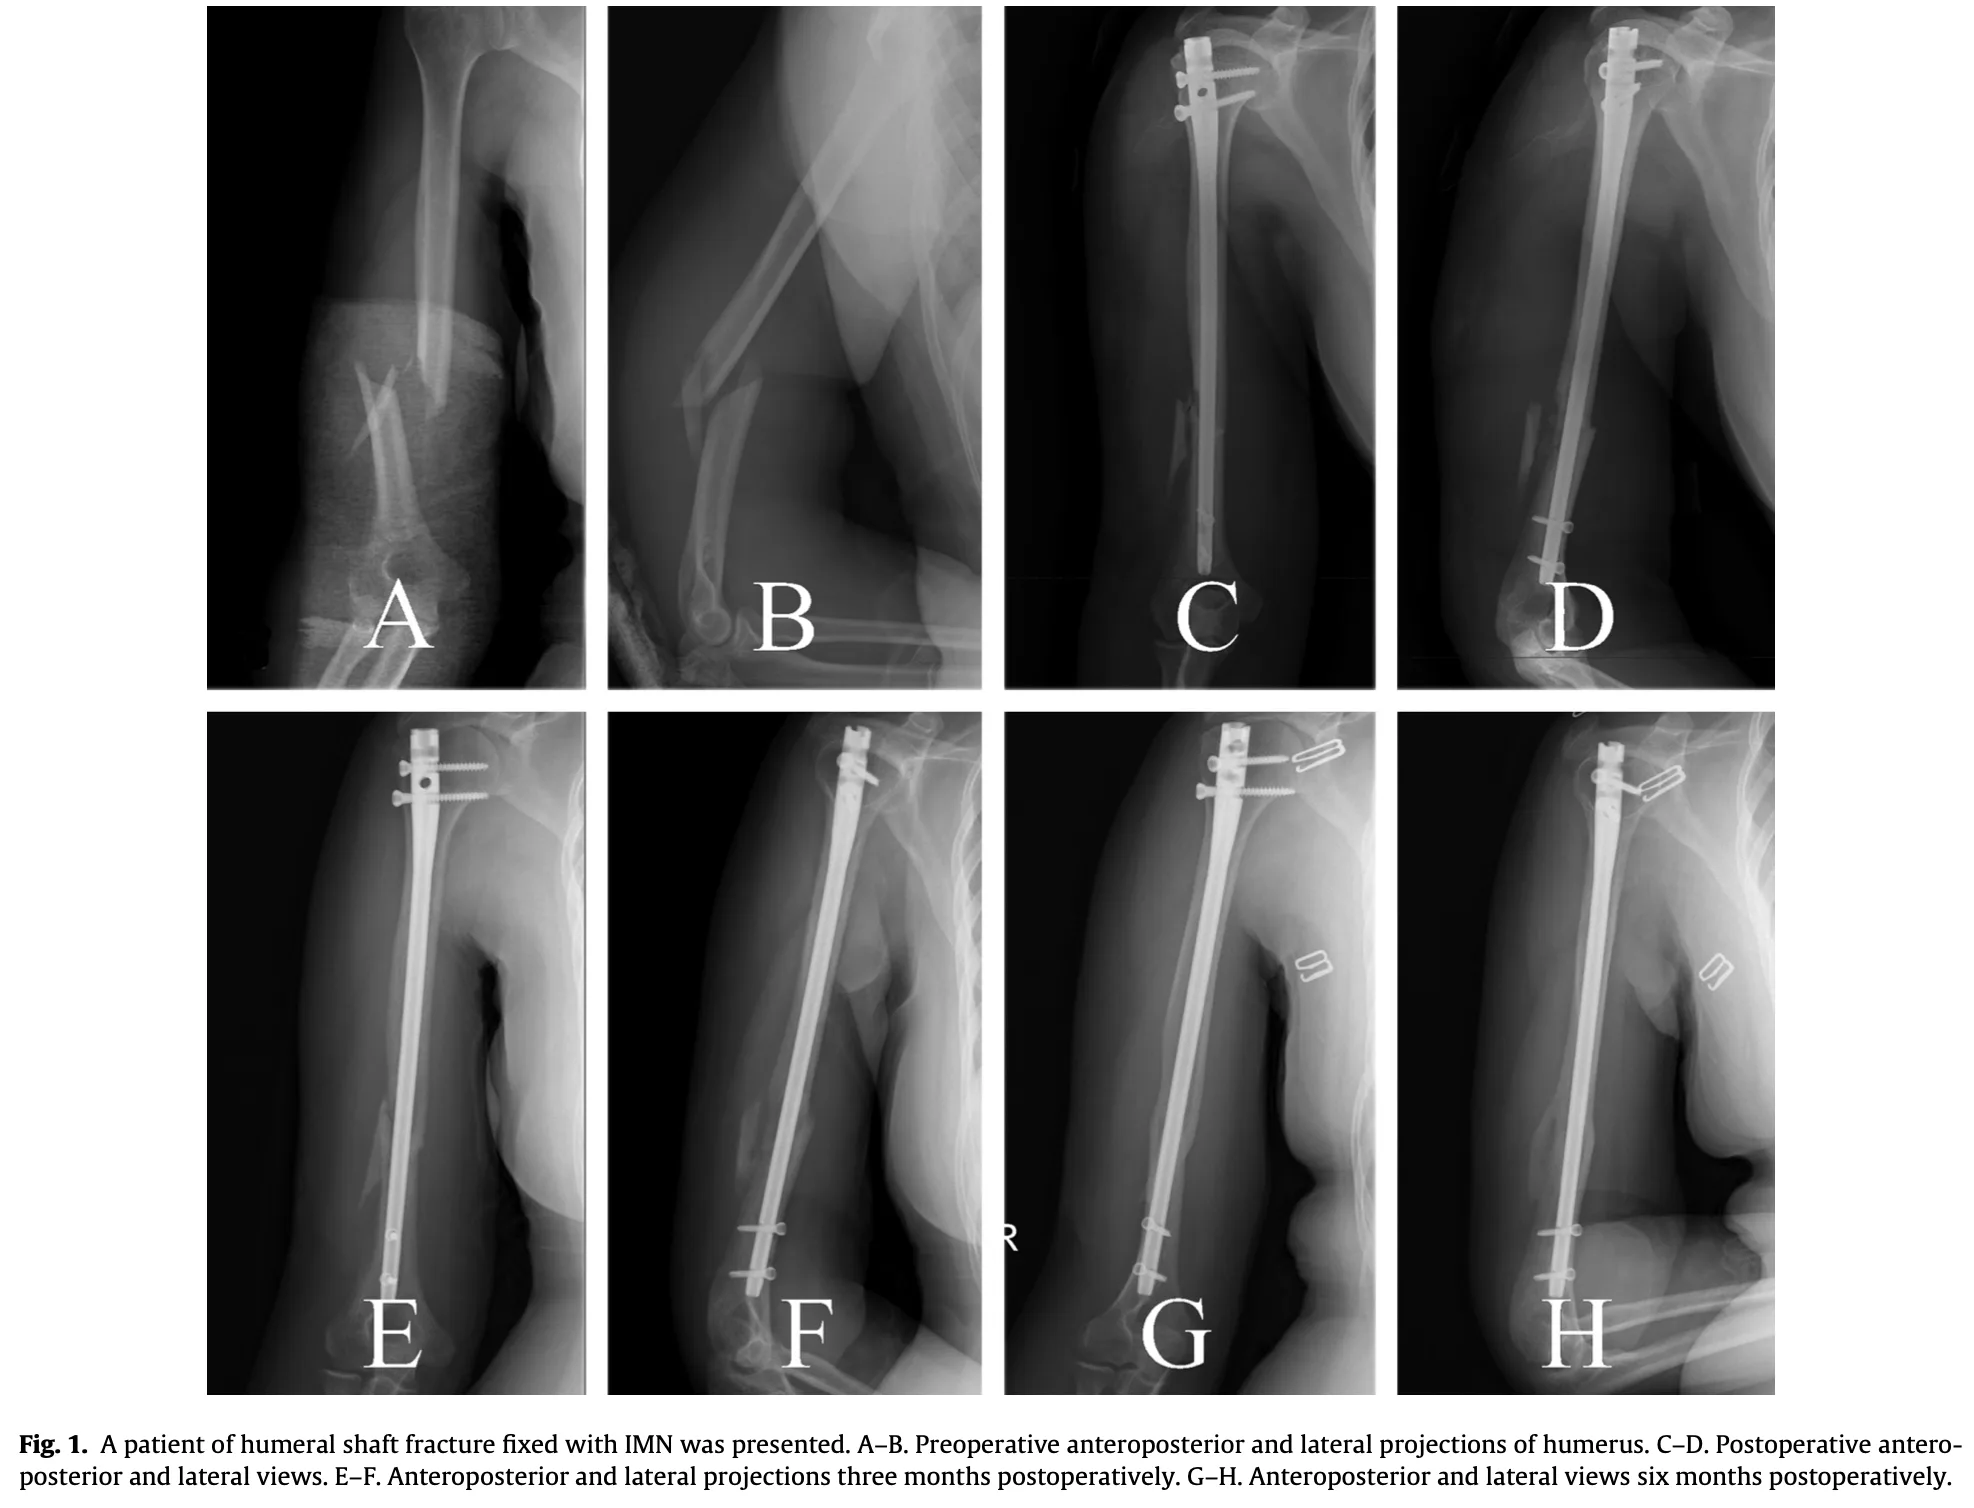

13時半からは上腕骨骨幹部骨折に対する手術.

手術部へ移動し, 助手として参加しました.

上腕骨の中央部を骨折した超高齢患者さんに対して, 骨内にチタン合金製の髄内釘を挿入し固定しました. 骨粗鬆症が強く, スクリューの効きがやや弱めでしたが, 手術は予定通り約1時間で無事終了しました.